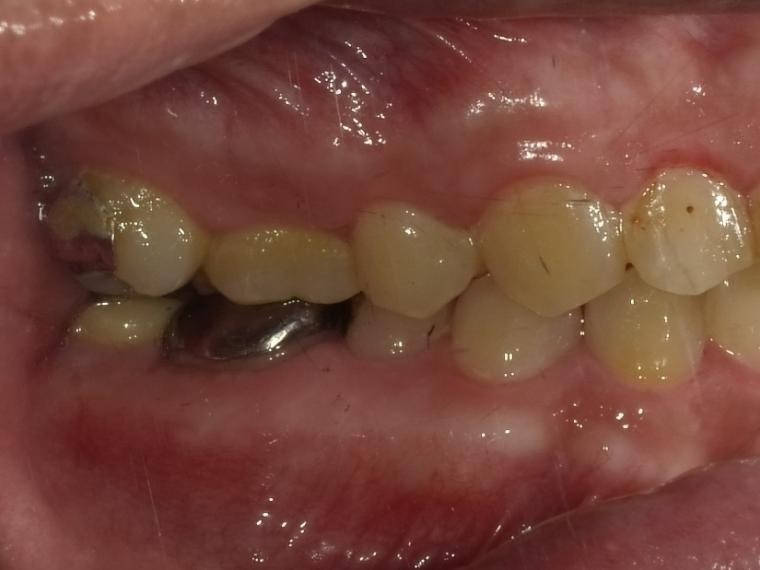

BEFORE

38歳男性/下1本欠損/インプラント埋込手術

右下奥歯が虫歯になってしまった為治療をすることになった患者さんです。

虫歯が進行していて、歯を保存出来なかったため歯を抜いて人工の骨を足してからインプラントを

1本埋込した患者さんです。